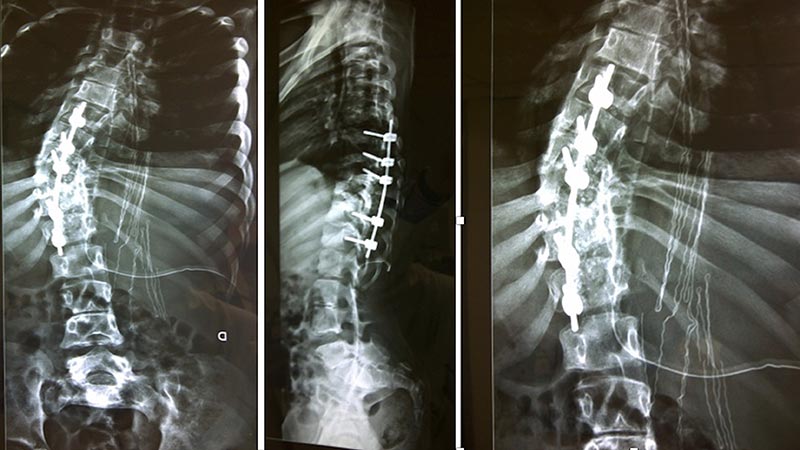

- Osteotomias: objetivo: correção em um único estágio. Problemas: dificuldade técnica riscos em relação a perda sanguínea, tempo cirúrgico, dano neurológico. Exemplos: Vertebrectomias: tipo 1: egg-shell, tipo 2: hemivertebrectomia, tipo 3: vertebrectomia total. Vertebrectomia total: remove toda a vértebra, inclui disco acima e abaixo; indicada se curva aguda e fixa acima de 100 graus (exemplo figura 11).

Figura 11. Ressecção de hemivertebra